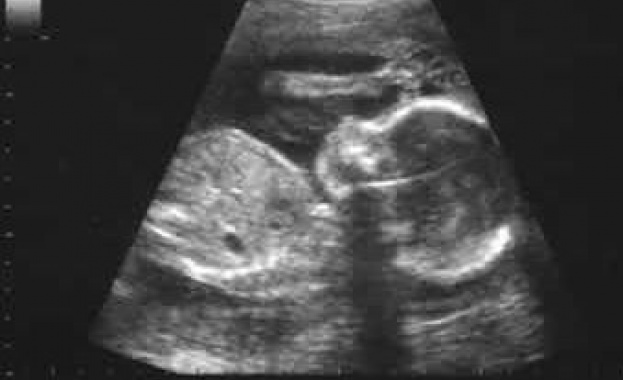

Преди дни стана известно, че бившият здравен министър д-р Таня Андреева, напълно непрозрачно, без мотиви и без дебат, е взела решение за промяна на границата между раждане и аборт. Досега в стандарта по акушерство и гинекология за живородено дете се смяташе такова над 600 г и/или над 22 гестационна седмица (г.с.), а по новия стандарт критерият се променя на над 800 грама или 26 г.с.

По досегашната наредба бебе, родено с признаци на кръвна циркулация с тегло над 600 грама и/или навършени 22 г.с., се считаше за живородено и като такова получаваше акт за раждане, ЕГН и в случай на смърт - акт за смърт, с който можеше да бъде погребано или кремирано. При сегашната наредба бебе, родено живо с тегло под 800 грама и преди навършени 26 г.с., не се счита за живородено до навършване на тридневна възраст. Едва тогава то може да бъде третирано като правен субект и да се възползва от правата си да получи акт за раждане, ЕГН и в случай на смърт - акт за смърт.

Много бебета ще попаднат в сивата зона между 600 и 800 грама и 22-ра и 26-та г.с. Със сигурност някои от тях няма да преживеят три денонощия и ще бъдат третирани като "абортен плод" - тоест, сякаш никога не са живели - независимо, че обективно, но и на първо място за родителите си, те, разбира се, са били живи, а след това са починали - и съответно би трябвало да се възползват от правото на всички човеци - да бъдат назовани, да бъдат запомнени и да бъдат изпратени.